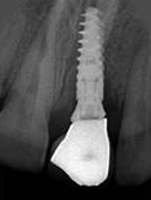

X-ray of Implant + Abutment

Single Tooth Implant

X-ray of Implant +

Abutment + Prosthesis

Placement of Bone Grafting

Abutment+ Prosthesis